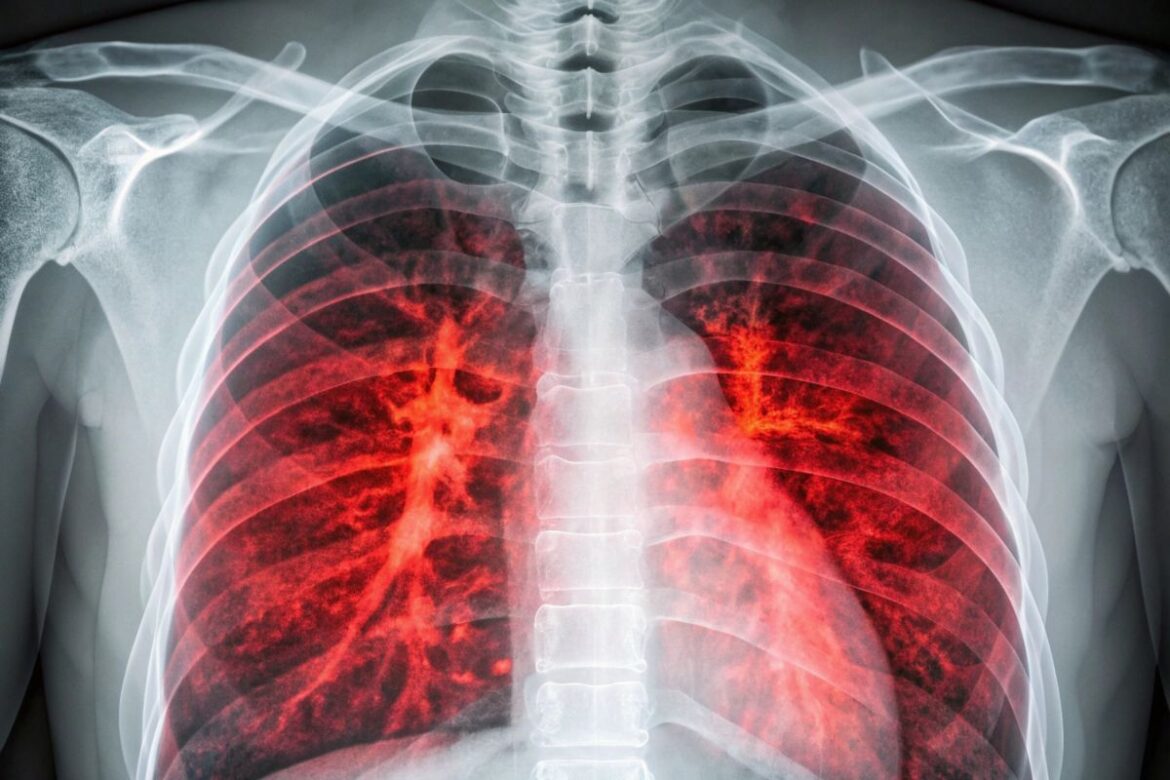

Lung cancer diagnostics is a complex, multi-stage process that enables detection of the disease, assessment of its advancement, and selection of the most effective treatment methods. Early diagnosis is crucial, as it greatly increases the chance of sustained cancer remission or prolonged survival. The diagnostic process usually starts with an interview and basic imaging tests, particularly for patients at risk or showing suggestive symptoms. The most common screening tool is low-dose computed tomography (LDCT) of the chest, which has much higher sensitivity than a standard chest X-ray and enables the detection of even very small cancerous changes. LDCT screening is especially recommended for people over 50 with a significant history of smoking. If abnormalities are found, diagnostics continue with more precise, advanced tests like standard computed tomography (CT), magnetic resonance imaging (MRI) for assessing possible brain spread, or positron emission tomography (PET-CT), which pinpoints cancer foci throughout the body and assesses cancer stage. The next step is obtaining tissue samples, essential for confirming diagnosis and determining the type of lung cancer. The most commonly used method is bronchoscopy – an endoscopic examination of the airways during which tissue is collected for histopathological testing. For peripheral lesions, fine-needle biopsy under ultrasound (ultrasound) or CT guidance can be used. Besides traditional biopsies, modern techniques such as liquid biopsy, based on analysing tumour DNA circulating in the blood, are playing an increasingly important role for non-invasive genetic testing and targeted therapy selection.